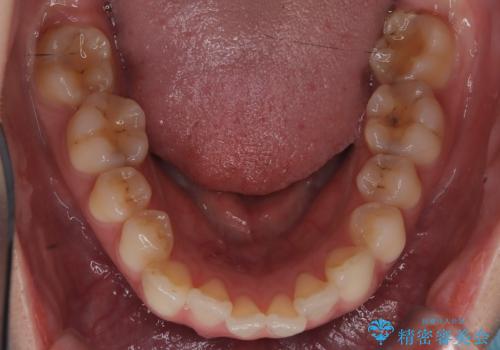

- 治療計画

今回のワイヤー矯正治療では、抜歯せずに歯を並べるスペースを作るため、特殊な小さなインプラントであるアンカースクリュー(TAD)を一時的に使用しました。このアンカースクリューを固定源として、奥歯(臼歯部)全体を後方へ遠心移動させました。従来の矯正では難しかったこの奥歯の移動を確実に行うことで、前歯の八重歯を適切な位置に並べるスペースを確保。治療の結果、抜歯することなく右上の八重歯と叢生が解消され、機能的にも審美的にも整った美しい歯並びを獲得していただけました。